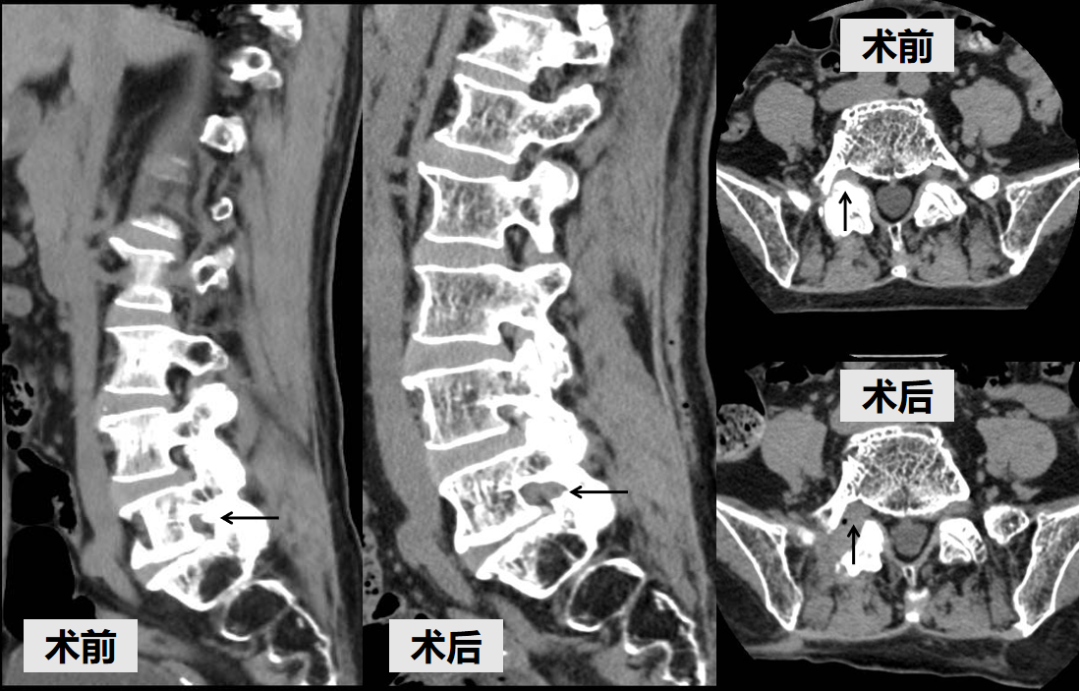

针对这一复杂病情,结合患者身体状况,团队决定采用目前先进的微创技术——单侧双通道内镜技术(UBE)切除增生骨质,解除神经压迫。相较于传统开放手术,UBE仅需两个1厘米左右的切口,通过椎旁入路精准到达病灶,切除增生的右侧S1上关节突尖部,扩大椎间孔,既能彻底解除神经压迫,又最大限度保护脊柱稳定性。手术顺利完成,术后次日苏女士即感右下肢轻松,坐起吃饭30分钟也没有出现疼痛,“像卸下了千斤重担”。

术后CT

术前术后CT对比